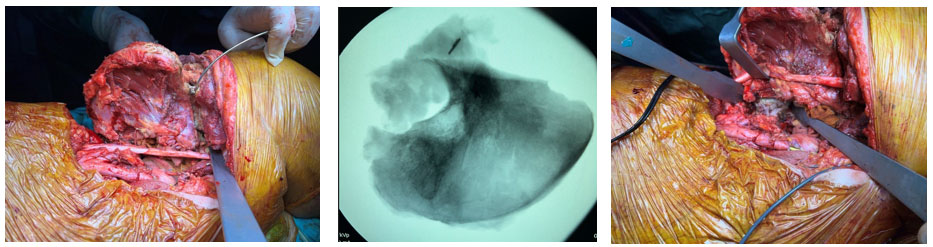

Ameliyat esnası: Tümörün sigmoid kolon, üreter ve iliak kanat invazyonu

Ameliyat esnası: Tümörle birlikte eksternal iliak arter ven’in rezeke edilmesi ve sentetik greft ile by-pass uygulanması

Ameliyat esnası: Kemik kesilerinin yapılması ve çıkarılan tümör dokusunun skopi görüntüsü